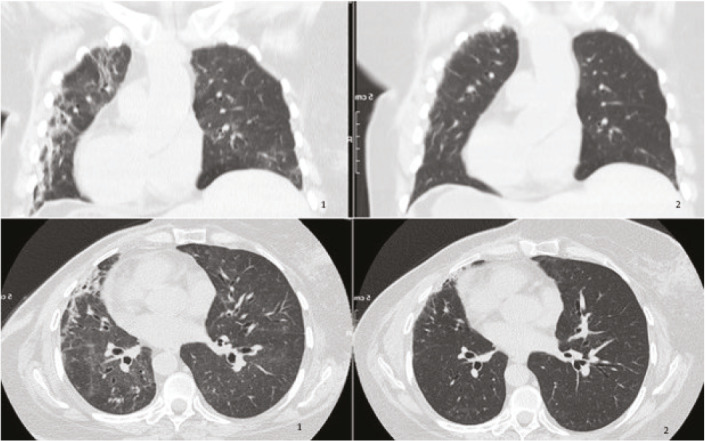

Can Pirfenidone and Nintedanib Be Alternative Treatment Options for Radiation Pneumonitis?

Abstract Image